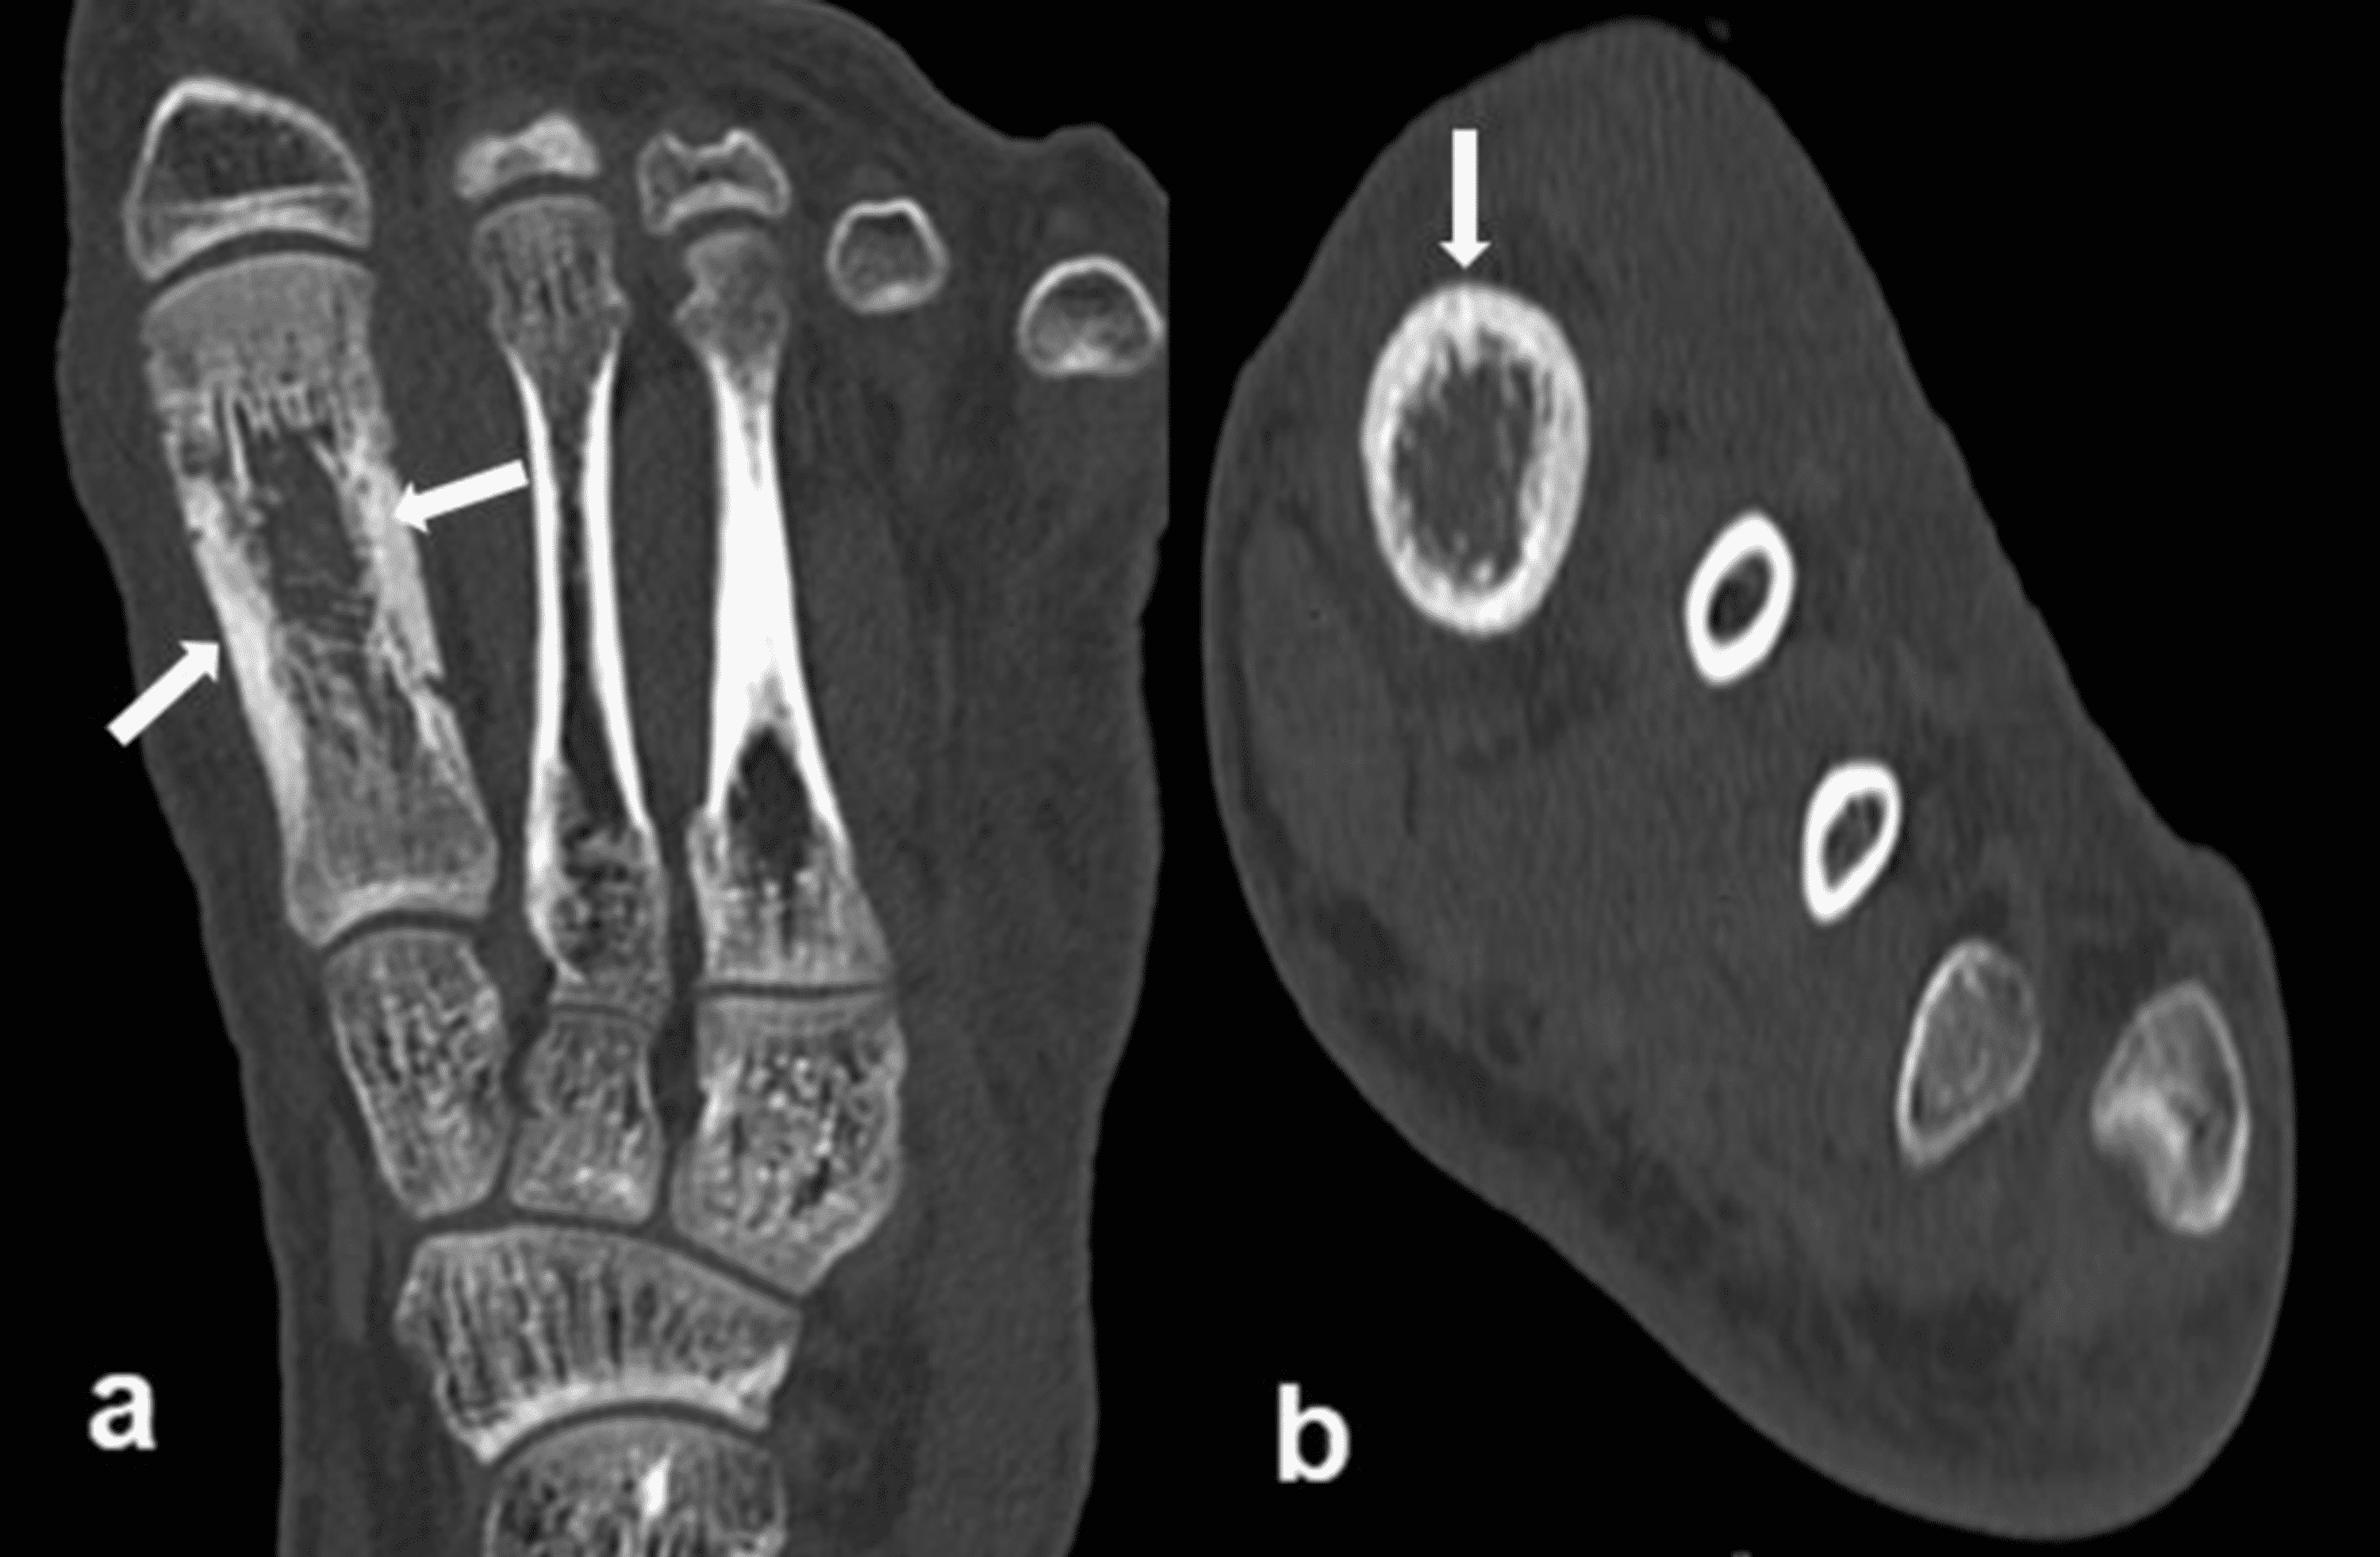

From www.ctisus.com

Osteomyelitis Involves the Calcaneus and the Cuboid Musculoskeletal Osteomyelitis Case From a case of acute osteomyelitis in a tarsal bone under an infected ulcer in a diabetic patient, we can observe distinct. In the described case of osteomyelitis, the patient presented with pain, functional limitation, and elevation of. Symptoms of acute osteomyelitis include pain, fever, and edema of the. This case presentation describes a toddler who presented to the emergency. Osteomyelitis Case.